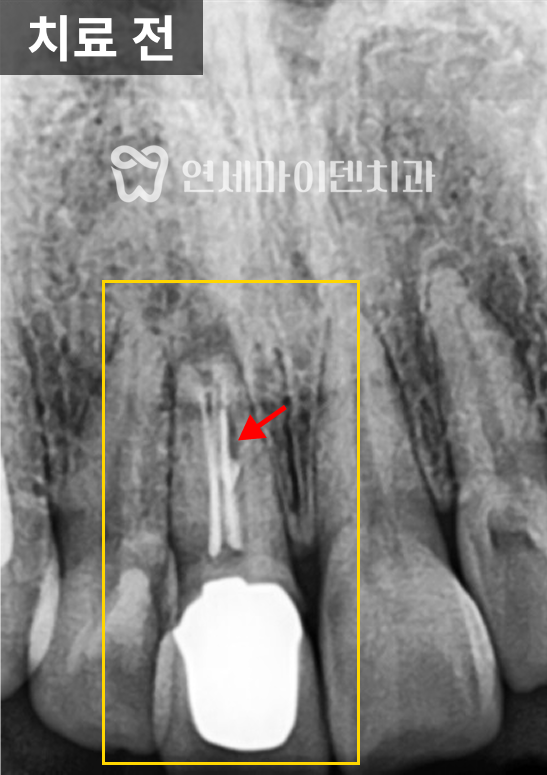

살펴보니 과거에 받으셨던 신경치료의 퀄리티가 아쉬운 부분이 있었습니다.

신경관뿌리까지 치료가 되어있지 않고, 중간에 갭이 보였습니다.

치료를 조금만 하면 개선의 여지가 있겠다는 생각이 들어, 우선은 재신경치료를 하기로 했습니다.

그리고 앞쪽 치아의 신경치료 방식을 보니 거타포차 콘(GP cone)을 하나씩 삽입하는 오래된 방식으로 이뤄져 있었습니다. 오래된 방식이라고 반드시 나쁜 것은 아닙니다. 다만 현재 훨씬 개선된 치료법이 존재하기 때문에 환자분들께서 더 완성도 높은 치료를 받으실 수 있습니다.

거타퍼차 콘(GP cone)을 하나씩 꽂는 방식이 아닌, 수직 가압 충전법을 사용하여 거타퍼차 콘을 녹여 충전하는 현대적 방식으로 진행하였습니다. 레진 충전시에도 임시 재료 없이 원칙적인 치료로 진행했습니다.